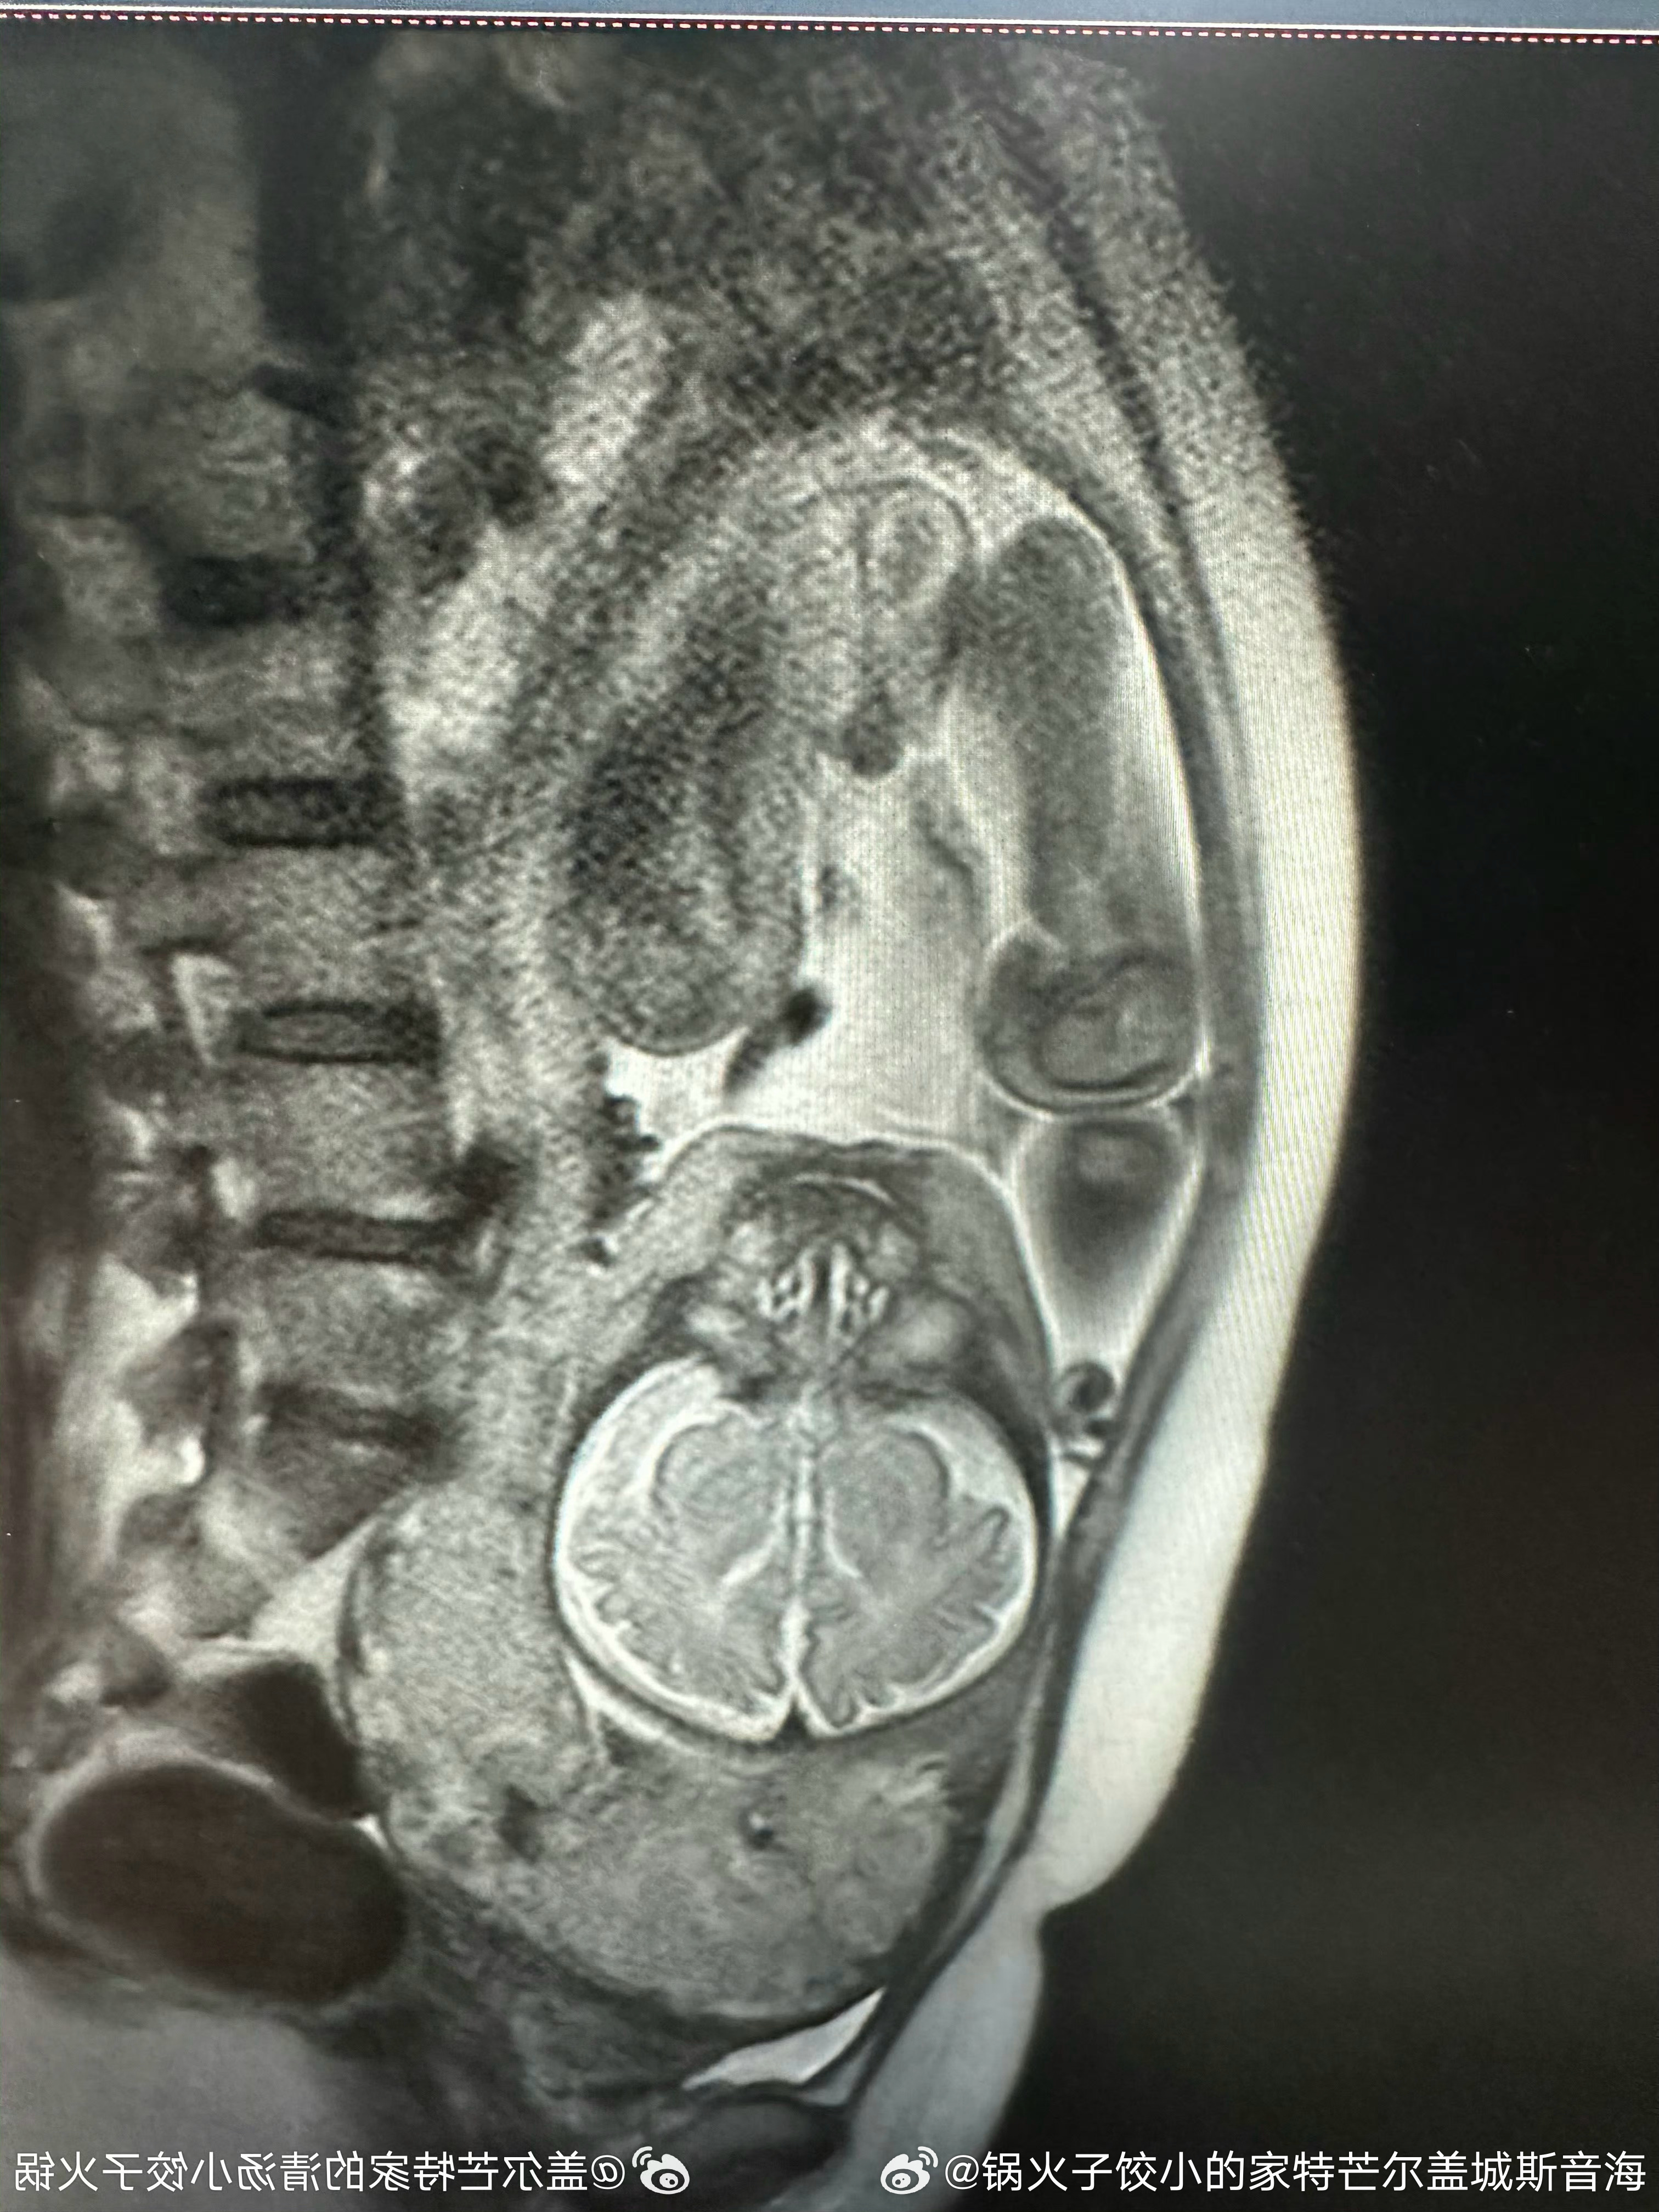

10:31 02˙21˙3202儿孩男小个是还!爱可多,宝宝小的下磁核